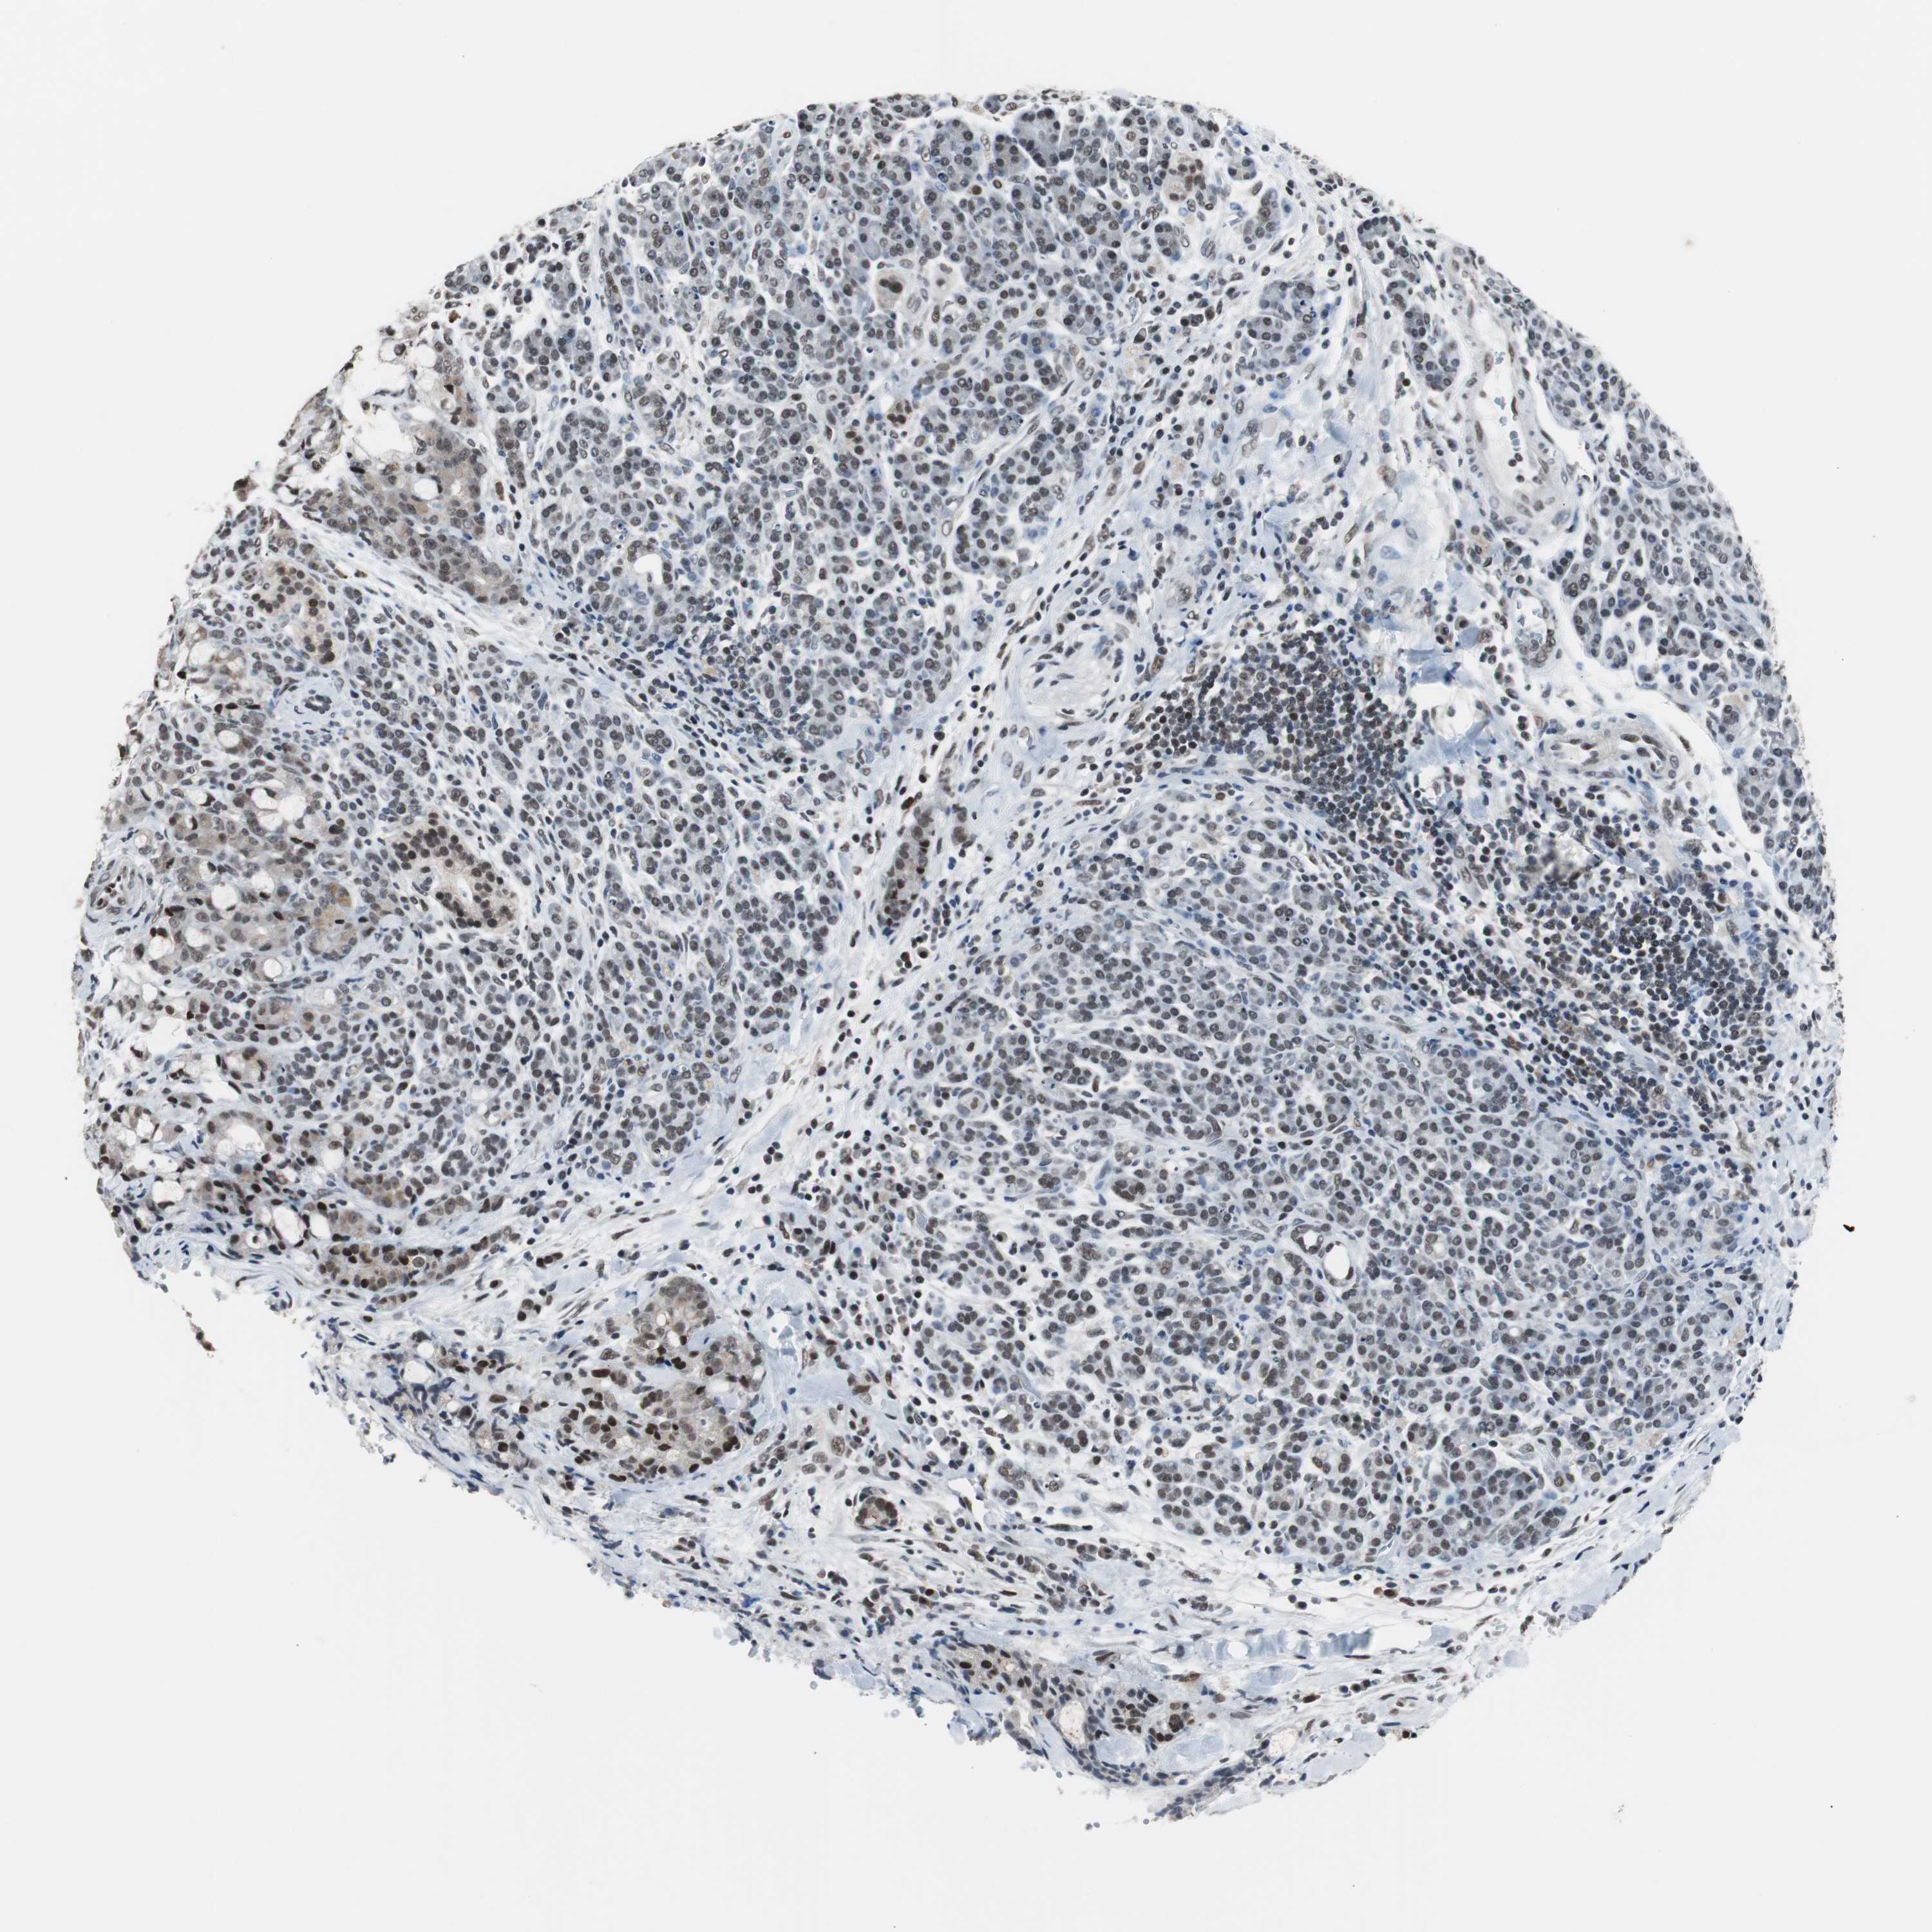

PANCREATIC CANCER - Protein expressioni

A mouse-over function shows sample information and annotation data. Click on an image to view it in a full screen mode. Samples can be filtered based on level of antibody staining by selecting one or several of the following categories: high, medium, low and not detected. The assay and annotation is described here.

Note that samples used for immunohistochemistry by the Human Protein Atlas do not correspond to samples in the TCGA dataset.

Antibody stainingi

Antibody staining in the annotated cell types in the current human tissue is reported as not detected, low, medium, or high, based on conventional immunohistochemistry profiling in selected tissues. This score is based on the combination of the staining intensity and fraction of stained cells.

Each image is clickable and will lead to virtual microscopy that enables deeper exploration of all samples and also displays staining intensity scores, fraction scores and subcellular localization as well as patient and tissue information for each sample.

Antibody HPA006429

Staining

High

Medium

Low

Not detected

Intensity

Strong

Moderate

Weak

Negative

Quantity

>75%

75%-25%

<25%

None

Location

Nuclear

Cytoplasmic/membranous

Cytoplasmic/membranous,nuclear

Adenocarcinoma, NOS

Adenocarcinoma, metastatic, NOS